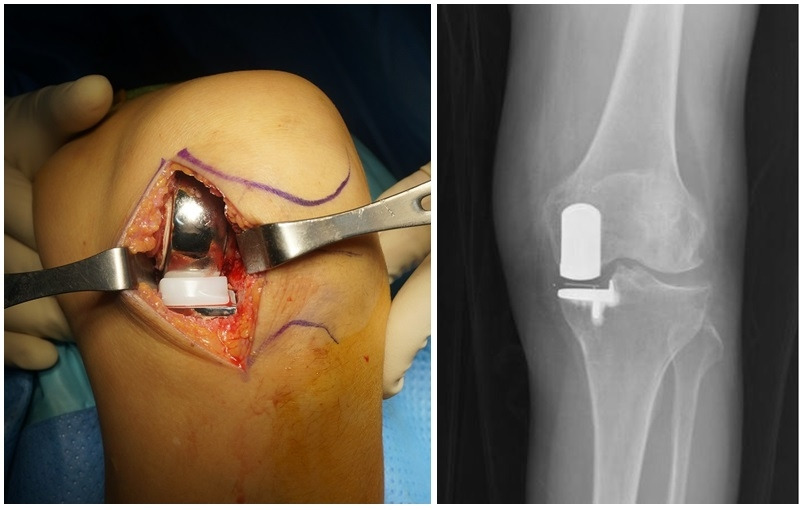

수술적 방법으로 가장 간단한 것은 관절 내시경 시술이라고도 칭하는 관절경 수술입니다. 무릎 관절 내부로 직경 4~5mm의 내시경을 넣어 손상된 연골판을 정리하거나 떨어진 연골조각 등을 제거해 주는 방법입니다 (아래사진).

무릎 관절경 수술 장면

비교적 간단한 수술이지만 적응증에 맞지 않는 경우엔 좋은 결과를 못 볼 수도 있습니다. 특히 유의해야 할 점은 잠김현상(locking, 갑자기 무릎이 구부려지지도 않고 펴지지도 않는 현상. 파열된 연골판 조각이 위아래의 뼈 사이에 끼여 발생)이 없는 단순 퇴행성 반월상연골 파열인 경우에는 관절경 수술이나 비수술적 치료 결과에 별 차이가 없으니 서둘러 수술할 필요는 없습니다 [24,25,26].

비교적 최신 수술방법인 ‘부분치환술’은 손상된 관절의 일부분만 정밀하게 다듬어낸 후 사이즈가 매우 작은 인공관절로 대체하는 획기적인 수술 방법으로 무릎 관절 인대들은 손대지 않으므로 정상적인 무릎 기능이 유지되어 걸음걸이가 자연스럽고, 양반자세를 하고 앉거나 쪼그려 앉는 데 별 무리가 없게 됩니다. 따라서 무릎을 많이 구부리는 생활습관을 가진 동양인, 특히 우리나라 사람들에게 아주 적합한 수술 방법입니다. 수술 부위도 5-6cm으로 작고, 무릎 조직의 일부분만 제거하기에, 수술 다음날 보조기도 없이 혼자 걸을 수 있을 정도로 회복이 빠른 것이 부분치환술의 장점입니다. 하지만 매우 정밀한 수술이라 경험이 적은 의사가 수술할 땐 여러가지 합병증이 생길 수 있다는 점을 염두에 두셔야 합니다 [30].

'부분치환술' 술 중 사진 & 술 후 X-ray

* 부분치환술 후 양반다리, 쪼그려 앉기, 꿇어 앉기가 가능해진 실제 환자 사진.